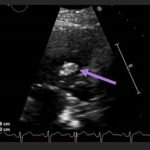

Endovascular coil embolization continues to become a more frequent modality of addressing hemorrhage and bleeding in patients. Migration refers to the coil unraveling or moving from the original embolization site. Migration of a coil is a known complication which can lead to serious consequences based on where the coil migrates. Despite increasing efforts to improve safety and technique, the risk of migration remains. We present a case of an embolization coil that migrated to the right ventricle, which was incidentally found roughly 2 months after undergoing an interventional radiology procedure for gastric variceal bleeding. The patient presented to the emergency department with dyspnea and abdominal pain. Unique images were obtained during his visit and in subsequent follow-up. As use of vascular embolization coils continues to become more commonplace, understanding the risks and complications of these procedures remains an important aspect of providing care for patients once they have left the interventional radiology suite. Coil migration should be a differential to consider in patients who present to the emergency department with signs or symptoms of arrhythmia or pulmonary embolism who have undergone a coil embolization procedure.